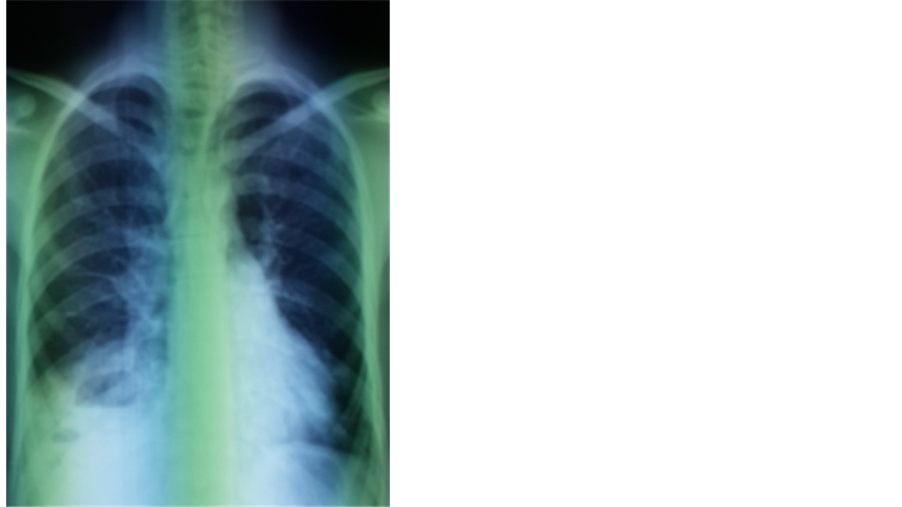

A 19-year-old North African patient, born of a non-consanguineous marriage, is the eldest in a family of three, his two brothers are healthy. He was admitted in an array of severe pneumonia consisting of nux and moderate hemoptysis and right chest pain in context of fever sensations and decline in general health. In its history, it was found a notion of recurrent and dragging respiratory infections on a plot of bronchiectasis with a psychomotor retardation discovered at the age of 7 years old. Clinical examination noted polypnea to 35 cycles/minute (normal respiratory rate is 16 - 20 cycles/minute), a blood pressure at 110/60 mm Hg (the normal rate is <120 mmHg for systolic and <80 mmHg for diastolic), a fever at 39.8˚C, an oxygen saturation of 96% (normal rate is between 95% and 100%), and incomplete condensation syndrome in right basi-thoracic, a finger clubbing and failure to thrive at −2 SD, with cerebellar ataxia, ocular bobbing in neurological examination. The mucocutaneous examination noted ocular telangiectasia and in the ear lobes. A Chest X-ray showed opacity with air fluid level in right basithoracic, associated with blunting ipsilateral pleural cul-de-sac (Figure 1). Chest computerized tomography (CT) was objectified tissue density opacity with excavation and signs for bronchiectasis (Figure 2). Laboratory tests showed leukocytosis at 14,200 cells/mm3. C-reactive protein was very high at 256.75 mg/l. Probabilistic antibiotic therapy was started with amoxicillin clavulanic acid intravenously at 1000 mg/8 hours, without improvement after 48 hours. The search for Mycobacterium tuberculosis (BK) on direct microscopic examination was negative. The cytobacteriological sputum had isolated a gram-positive cocci in favor of Klebsiella pneumoniae resistant to penicillin but susceptible to cephalosporin. The patient was put under 3rd generation of cephalosporin with good clinical, biological and radiological outcome. Before the notion of repeated respiratory infection, bronchectasis, cerebellar ataxia, cutaneous telangiectasia, diagnosis of Ataxia Telangiectasia syndrome was discussed. The α-fetoprotein was high at 570 ng/ml. The search of combined immunodeficiency showed rates of IgA, IgM and IgG respectively at 7 g/l; 1.76 g/l; 11.3 g/l. The CD4/CD8 ratio was down to 0.6. Brain Magnetic Resonance Imaging (MRI) showed cerebellar atrophy. Oral consent was obtained from the patient’s family to publish this case.

Figure 1. Opacity with air fluid level in right basithoracic, associated with blunting ipsilateral pleural cul-de-sac.